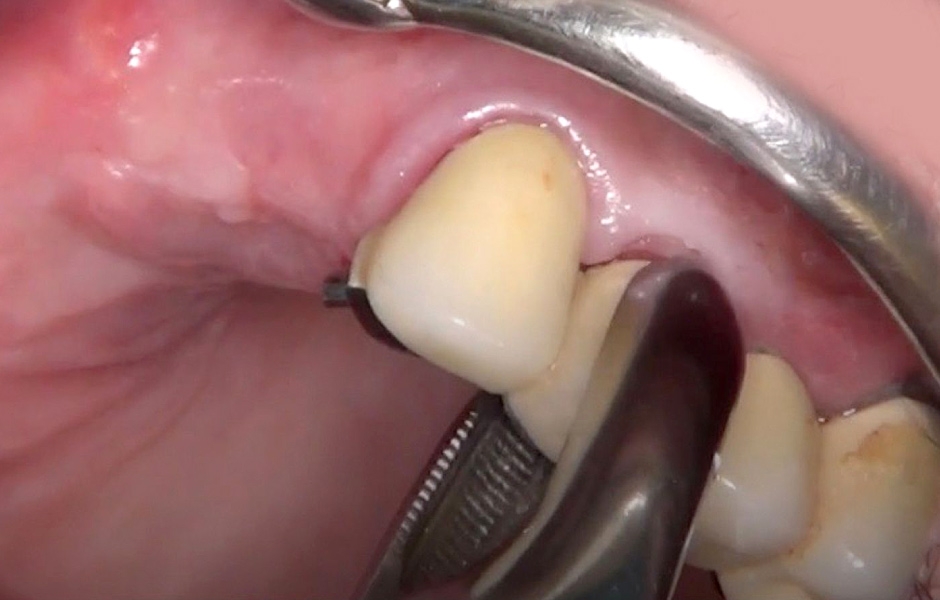

Dvě hodiny před zákrokem byly podány 2 g Augmentinu (amoxicilin/kyselina klavulanová) a pacient použil ústní vodu s 0,12 % chlorhexidinu 24 hodin před zákrokem. Byla aplikována lokální anestezie se 4 % artikainu a adrenalinem1:100 000. Následně byl odstraněn starý můstek a provedena atraumatická extrakce neperspektivních zubů (23, 24, 25 a 26) (obr. 18–20).

Obr. 18

Obr. 19

Obr. 20